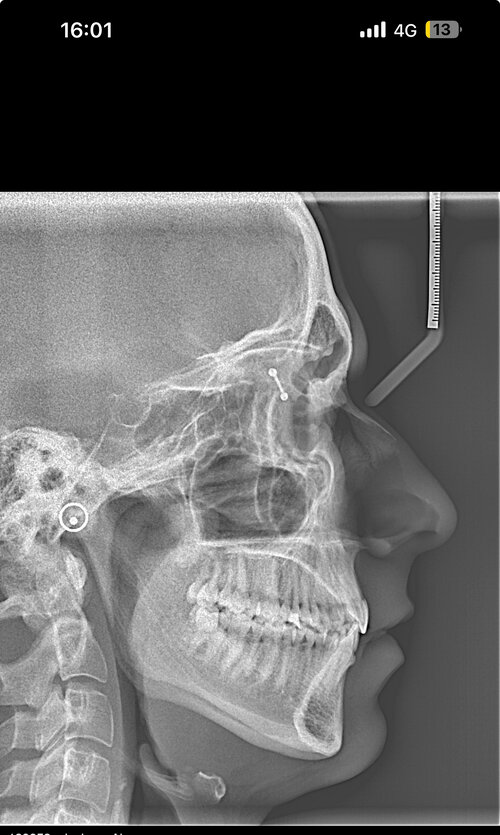

Hello, I’m looking for advice on genioplasty vs DJS. I was planned for a genio 7mm horizontal and squaring of chin on may 11th. I got a second opinion because I thought the oralmaxillofacila surgeon doing my genio might have been downplaying my mandible/maxilla recession. The second opinion oomfs surgeon said that genio would only be a camouflage and for my high expectations, might disappoint me, and I’m starting to think it will. My midface is flat and my mandible from side profile looks short and awful. The problem I have is DJS is a huge commitment for a bigger gain in a year-year and a half time. It’s a lot to take in. But I really don’t want to live my whole life with recessed jaws, I don’t want a soft youthful boyish look especially because I’m getting into my mid 20s, I hate my side profile a lot. Genio will help but I’m extremely worried I’ll be really disappointed, and I can’t really go back if I commit. Looking for advice on if I should go with the genio, see improvement now (which I care a lot about) and get a rhino/septoplasty to fix my deviated septum and be capped by by midface/mandible recession but decently improved, or If I should look awful for another year and a half with braces and my current recession but have the functional and aesthetic benefit of djs at the end. I have extremely bad breathing issues especially during exercise and pretty bad sleep issues, but I don’t know how much to that is down to allergies/deviated septum as opposed to airway issues. I just don’t know what to do, I’ll include my ceph/ct scans and side/front profile photos, would really appreciate guidance on what to do, was thinking of frauding with filler for a year before getting djs, or getting real structural change through rhino braces and genio that would all be down within 7-9 months, thankyou .

• IMG_3956.jpeg

IMG_3956.jpeg

958.3 KB · Views: 0